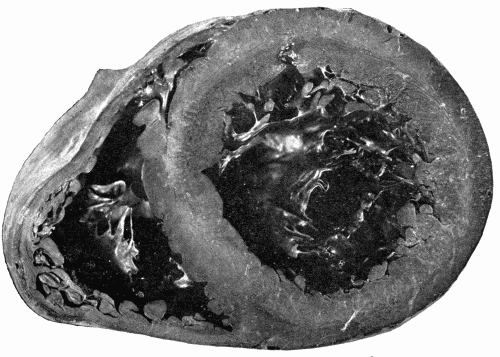

In the nodular form the lesions are found on the aorta and large branches particularly at or near the orifices of branching vessels. These nodules may increase in size, forming rather large, slightly raised plaques of yellowish-white color. They are, as a rule, irregularly scattered throughout the aorta and branches and tend to be more numerous and larger in the abdominal aorta. The initial lesion is in the media, consisting of an actual dissolution of this coat with rupture of the elastic fibers and infiltration with small round cells. There is thus a weak spot in the artery. Hypertrophy of the intimal cells takes place, layer upon layer being added in an attempt to strengthen the vessel at the injured place. Coincidently with this, there is thickening by a connective tissue growth in the adventitia. The process begins, at least in syphilis, around the terminals of the vasa vasorum. It will be recalled that the blood supply of the inner portion of the media comes[38] from within the vessel itself. As the intimal growth increases, the blood supply is cut off. The inevitable result is softening of the portion farthest from the lumen of the vessel. As a rule there has been a sufficient growth of connective tissue in the media and adventitia to repair the damage done to the media. This softening and dissolution gives rise to a granular debris composed of degenerated cells and fat. This is the so-called atheromatous abscess. There are no leucocytes as in ordinary pus. These "abscesses" are frequent and in rupturing leave open ulcers with smooth bases, the atheromatous ulcer. A further change which often takes place is calcification of the bases of the ulcers and calcification of the softened spots before rupture takes place. This only occurs in advanced cases. (See Fig. 3.)

Fig. 3.—Arteriosclerosis of the thoracic and abdominal aorta, showing irregular nodules, atheromatous plaques, denudation of the intima, thin plates of bone scattered throughout with spicules extending into the lumen of the vessel. Note the contraction of the openings of the large branches, the rough appearance of the aorta and the greater degree of sclerosis of the upper two-thirds, i. e., of the aorta above the diaphragm. This aorta in the recent state was much thickened and almost inelastic. Fig. 3.—Arteriosclerosis of the thoracic and abdominal aorta, showing irregular nodules, atheromatous plaques, denudation of the intima, thin plates of bone scattered throughout with spicules extending into the lumen of the vessel. Note the contraction of the openings of the large branches, the rough appearance of the aorta and the greater degree of sclerosis of the upper two-thirds, i. e., of the aorta above the diaphragm. This aorta in the recent state was much thickened and almost inelastic.

Fig. 4.—Arteriosclerosis of the arch of the aorta. Numerous calcified plaques, thickening and curling of the aortic valves, giving rise to insufficiency of the aortic valves. The aortic ring is rigid and not much dilated. (Milwaukee County Hospital.) Fig. 4.—Arteriosclerosis of the arch of the aorta. Numerous calcified plaques, thickening and curling of the aortic valves, giving rise to insufficiency of the aortic valves. The aortic ring is rigid and not much dilated. (Milwaukee County Hospital.)

Fig. 5.—Normal aorta. Compare with Fig. 3. Note the perfectly smooth, glossy appearance of the intima. The openings of all the intercostal arteries are distinctly seen. In the recent state this artery was highly elastic, capable of much stretching both transversely and longitudinally. Fig. 5.—Normal aorta. Compare with Fig. 3. Note the perfectly smooth, glossy appearance of the intima. The openings of all the intercostal arteries are distinctly seen. In the recent state this artery was highly elastic, capable of much stretching both transversely and longitudinally.